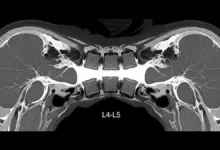

Exames de imagem não são obrigatórios para todos os pacientes.

Costumam ser mais úteis quando:

- A dor persiste apesar do tratamento inicial.

- Há sintomas neurológicos.

- Se suspeita de fratura, infecção, tumor.

- Existe planejamento de procedimento intervencionista ou cirurgia.